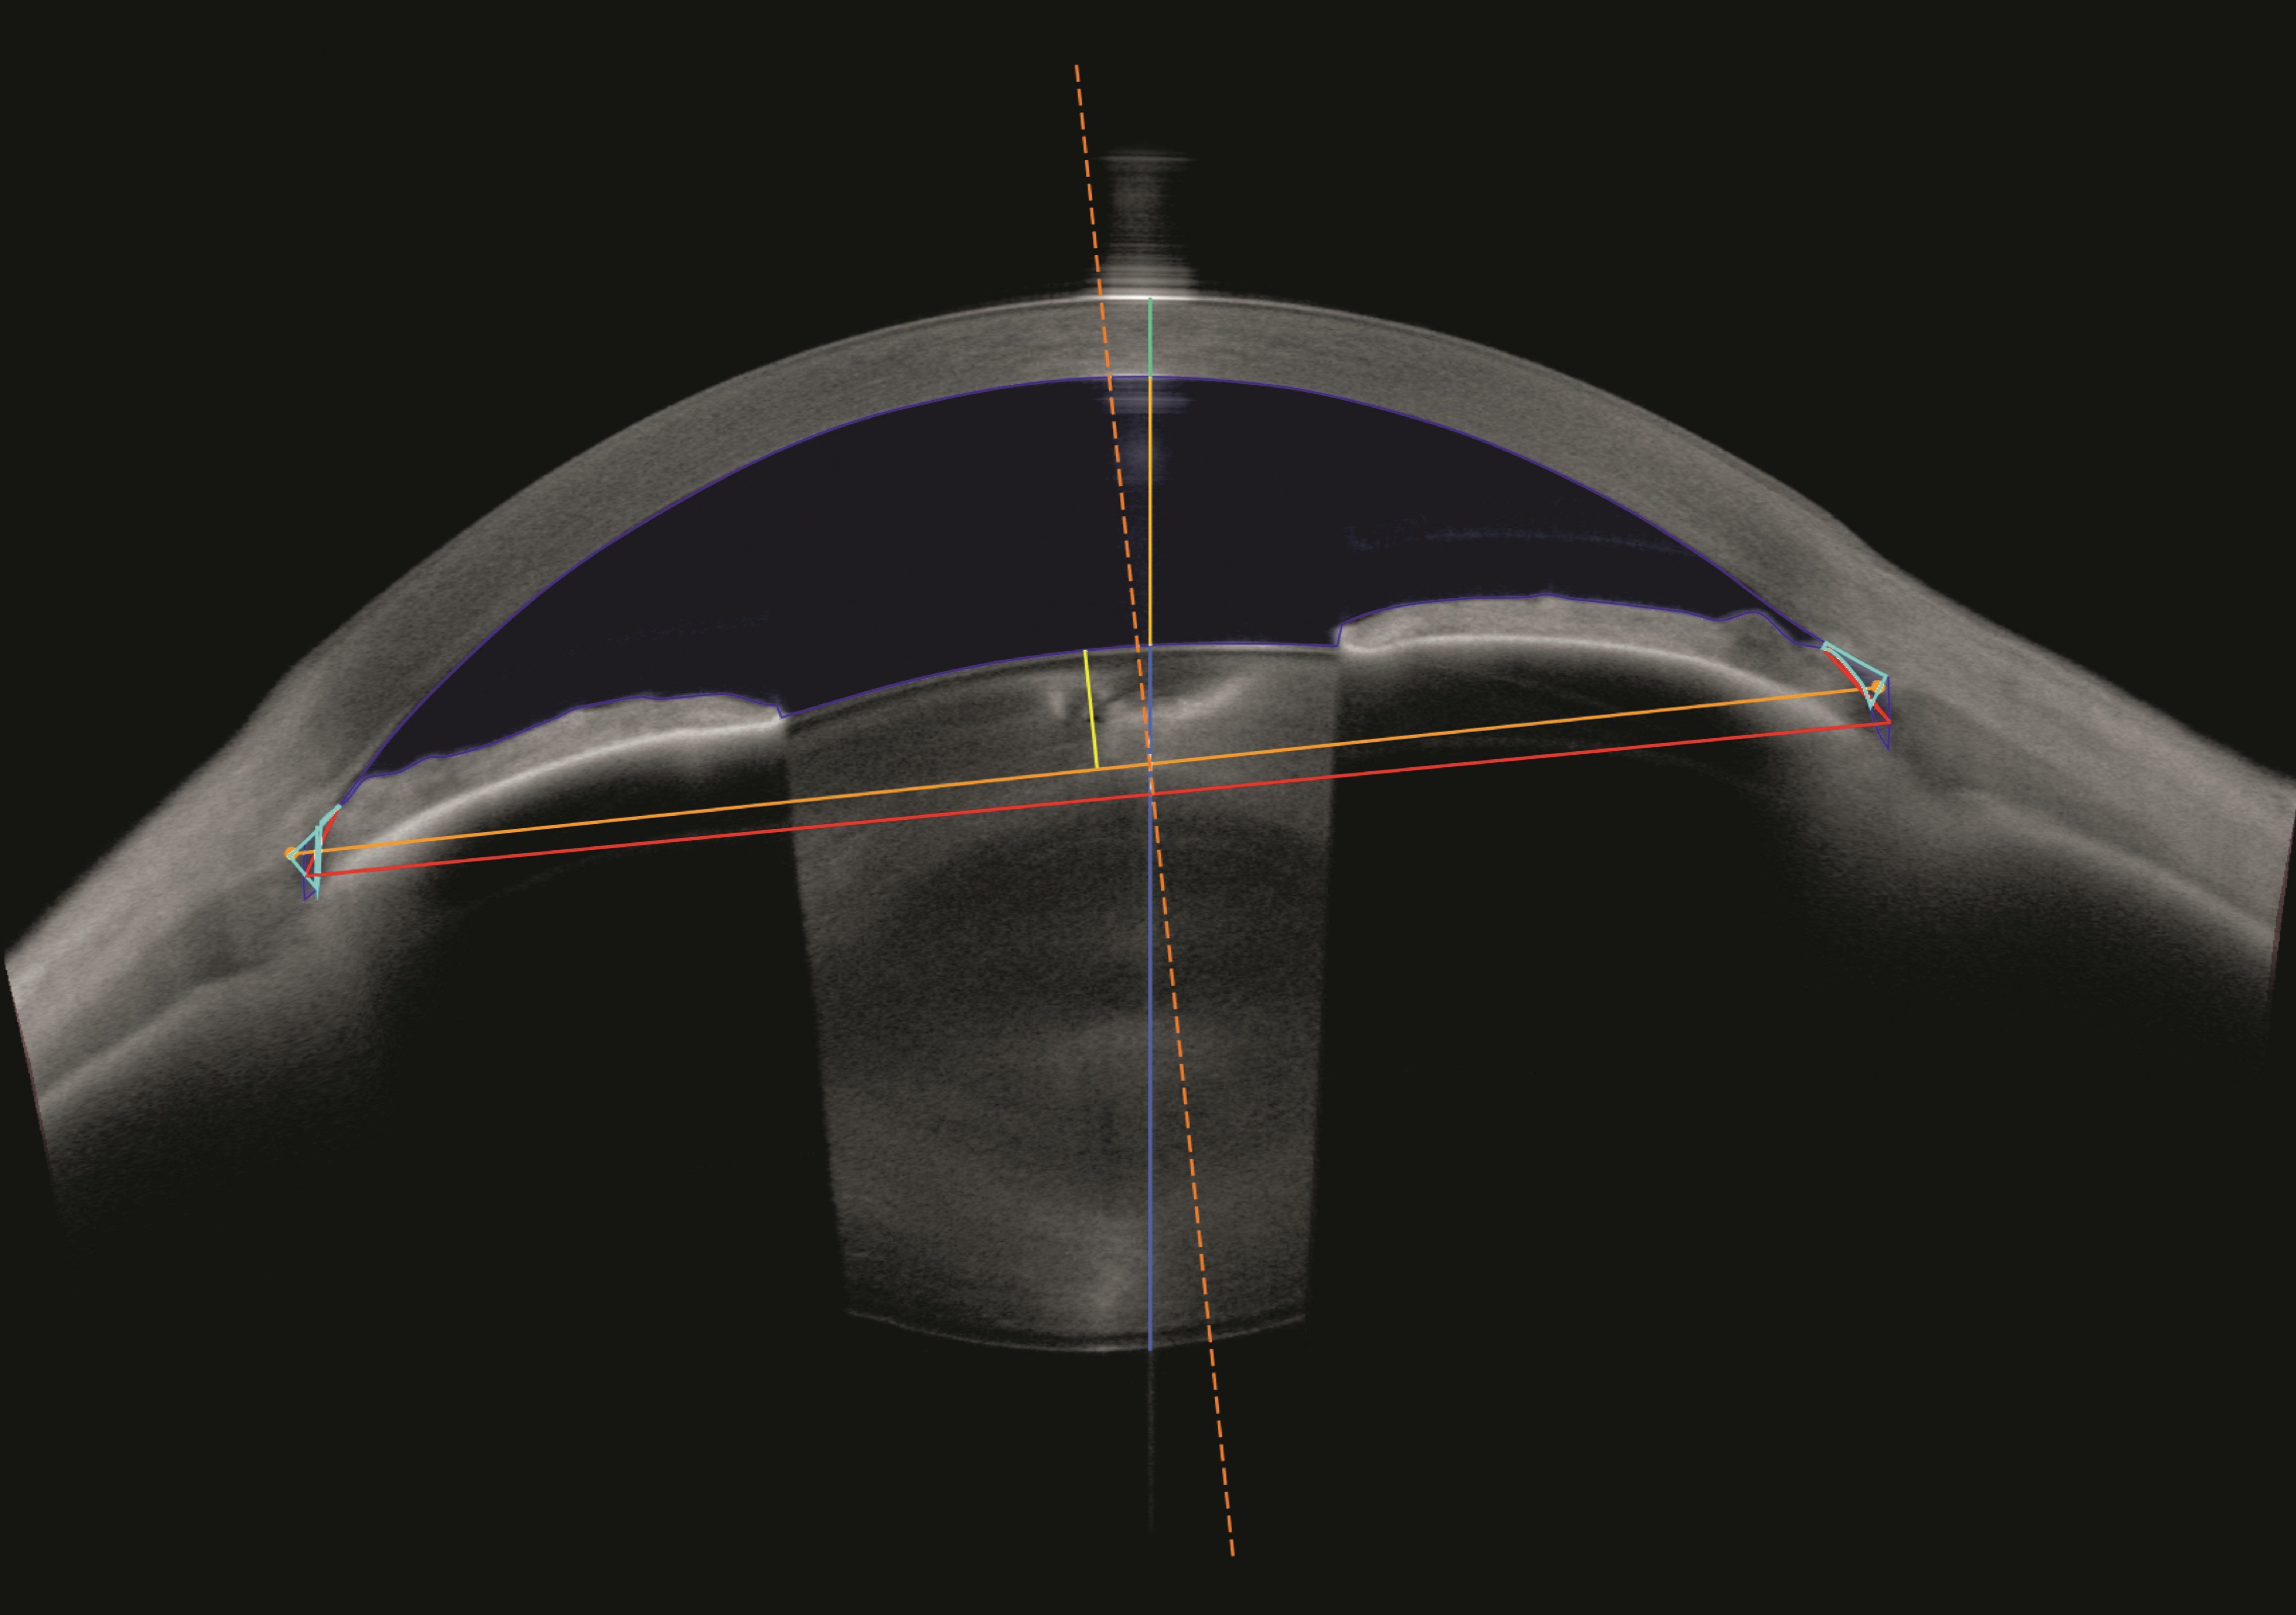

Als unverzichtbares Werkzeug für die Planung von Kataraktoperationen ermittelt ANTERION präzise biometrische Streckenmessungen sowie die gesamte Hornhautstärke, alles mit optimierter OCT-Technologie. So können Sie Ihre klinischen Ergebnisse selbst in den schwierigsten Fällen verbessern. Die OCT-Bilder helfen Ihnen dabei, Ihre Messungen zu bestätigen, sodass weniger Annahmen erforderlich sind.

Die Cataract App bietet sphärische und torische IOL-Berechnungen sowie Raytracing-Anwendungen und liefert die erforderlichen Daten zur Berechnung der für Ihre Patient:innen am besten geeigneten IOL, ohne dass Daten übertragen oder Geräte gewechselt werden müssen.